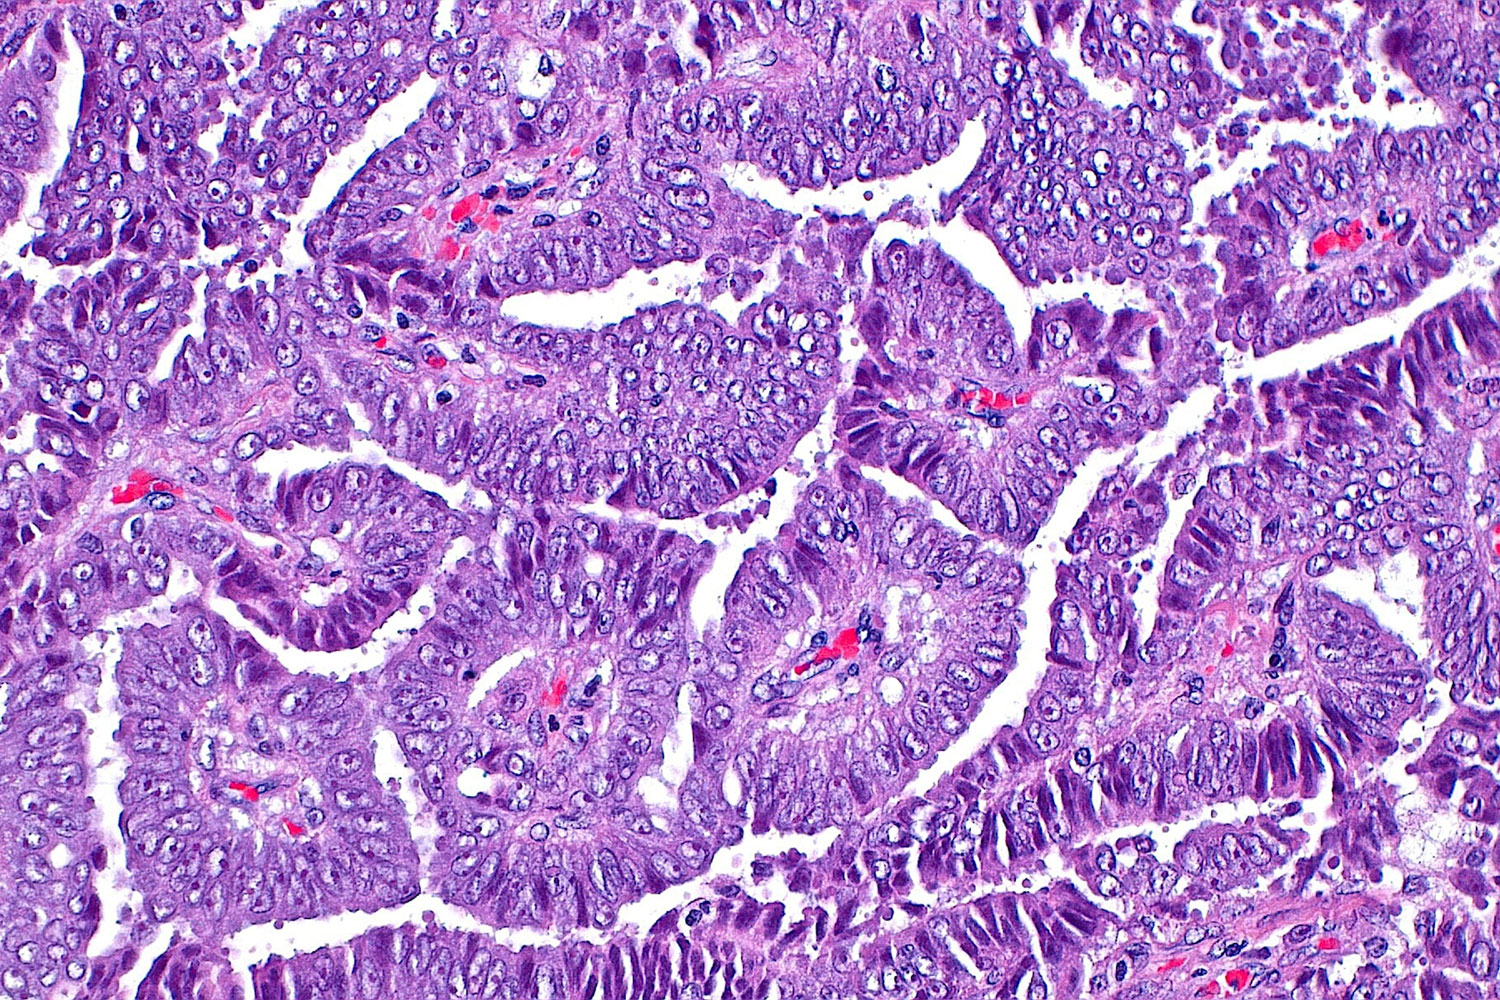

NYU Langone Health researchers found that a type of cell death caused by a buildup of highly reactive molecules suppresses...